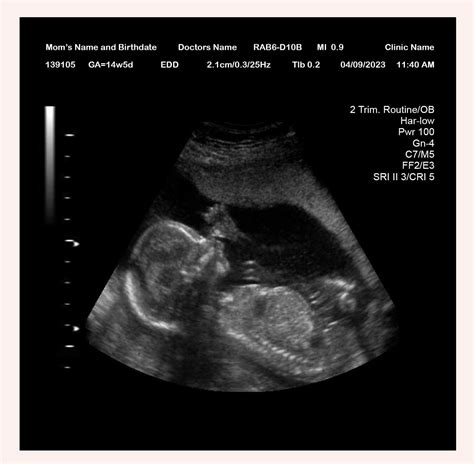

Pregnancy is an exciting journey filled with milestones, and one of the most anticipated moments is the 14 week sonogram. This ultrasound scan provides valuable insights into the development of the fetus and offers parents a glimpse into their baby's world. Understanding what to expect during a 14 week sonogram can help alleviate anxiety and enhance the overall experience.

A 14 week sonogram is an ultrasound examination performed around the 14th week of pregnancy. It is typically part of the routine prenatal care and is often referred to as the “nuchal translucency scan.” This scan is crucial for assessing the baby’s development and detecting any potential abnormalities.

At 14 weeks, the fetus undergoes significant developmental changes. Some of the key milestones include:

• The baby’s head is still large in proportion to the body, but the body is starting to catch up.

• The baby’s limbs are more defined, and the fingers and toes are visible.

• The baby’s facial features are becoming more distinct, with eyes moving closer together and ears almost in their final position.

• The baby’s heart is beating strongly, and the lungs are starting to form.

• The baby’s digestive system is developing, and the intestines are moving from the umbilical cord to the abdomen.